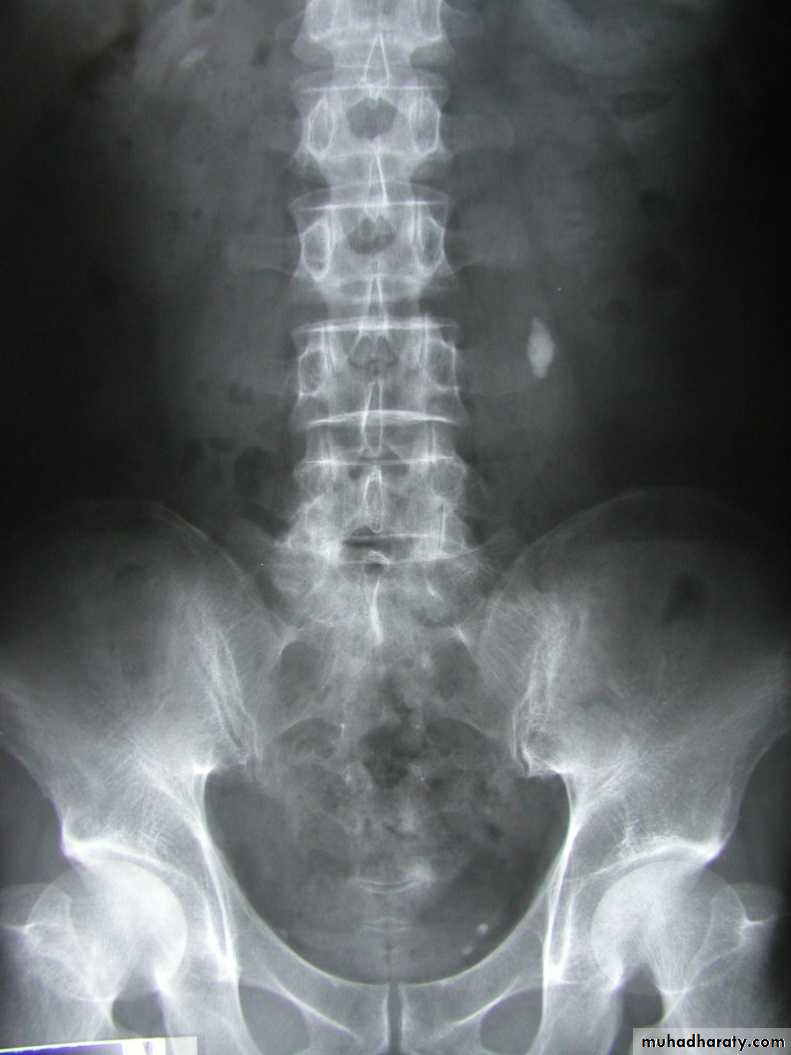

• Ddgx of stone on KUB :

• 1. Gall stone• 2. calfied LN , cartilage ,fibroid,

• 3. Phlebolith: round, lucent centre.